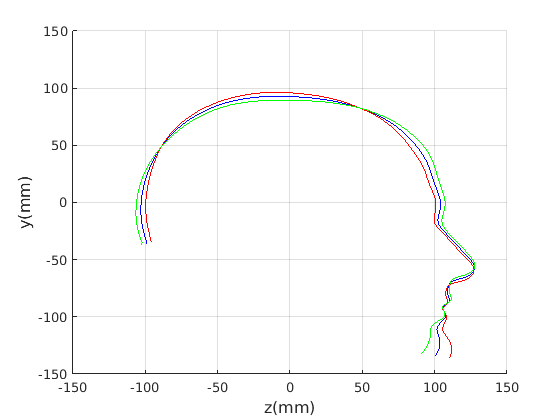

Figure 16 shows examples of the robust ellipse fit for four head profiles. The centre of the ellipse is used in a pose normalisation procedure where the ellipse centre is used as the origin of the profile and the angle from the ellipse centre to the nasion is fixed at -10 degrees. We call this Ellipse Centre - Nasion (ECN) pose normalisation and later compare this to GPA. The major and minor axes of the extracted ellipses are plotted as red and green lines respectively in Fig. 16.

|

Figure 17 shows all 100 profiles overlaid with the same alignment scheme. The median value of major ellipse axis and the ellipse centre-nasion angle differ by 3.6 degrees, so that when the nasion angle is fixed at -10 degrees, the median ellipse angle is -6.4 degrees (cf. -7.4 degrees with manual landmarking of the nasion). We noted regularity in the orientation of the fitted ellipse as is indicated by the clustering of the major (red) and minor (green) axes in Fig. 17 and the histogram of ellipse orientations in Fig. 18. For most people, the major axis of the ellipse is closely aligned with the y-axis (upright), and titled slightly forwards. A minority of heads (9%) in the training sample have their major ellipse axes closer to the vertical (these relatively tall and short heads are known as brachycephalic.) Ellipse axis clustering (relative to the fixed ellipse centre-nasion line) does not appear to be sharply defined. This is because many crania are close to circular in cross-section, making the orientation of these angles sensitive to small changes in shape from one person to the next. Note also the variation at the back of the head due to a variety of hair styles, some of which protrude from under the cap. We limit the region over which we model the cranial shape in order to crop this unwanted data out.